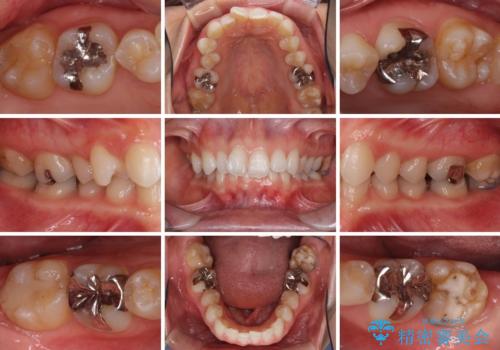

- 奥歯の虫歯と前歯のデコボコや突出感を気にして来院された患者様です。

上顎歯列が、下顎に対して前方にありましたが、口元に出っ歯の印象がなかったため、親知らずを抜歯した上で、上顎歯列全体を後方に移動させることとしました。

咬合力が強いため、アンカースクリューを使用し、ワイヤー装置にて矯正治療を行うこととしました。

矯正治療後は、奥歯の虫歯や銀歯を補綴・修復治療することとしました。